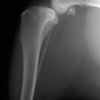

術前左後肢側面像

術前正面像

術前のTPAは左後肢33.1°右後肢26.8°でしたがTPLO実施により左後肢5.5°右後肢12°に矯正されました。